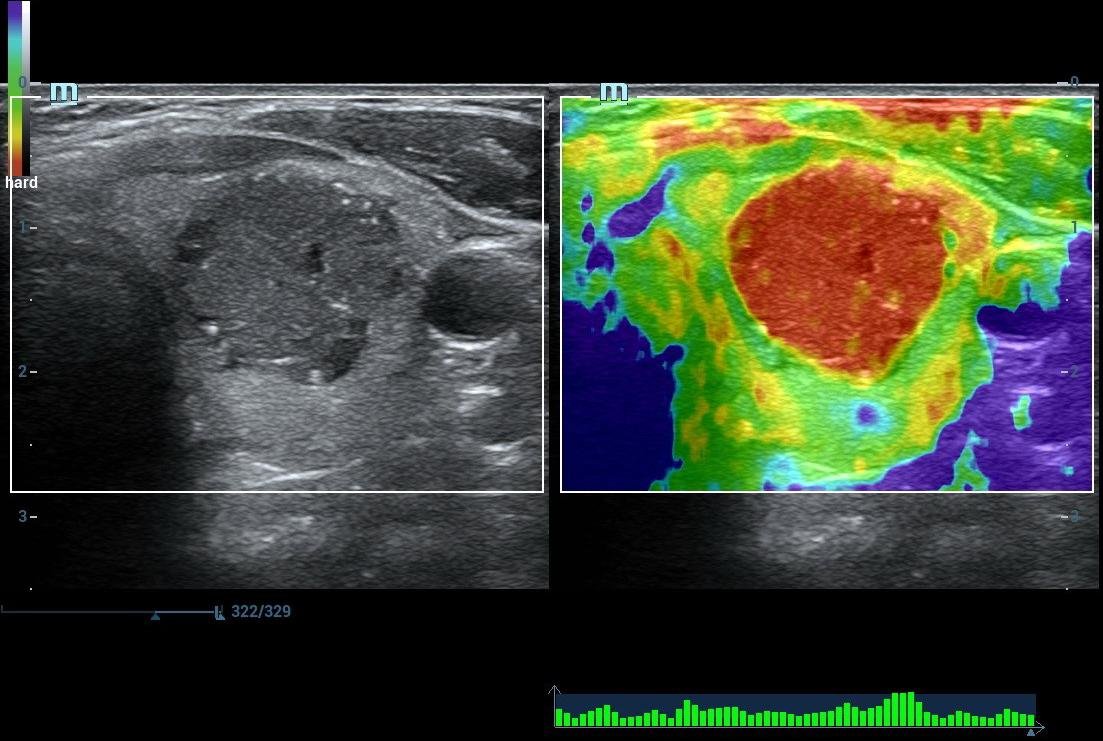

• High End SHEAR WAVE ELASTOGRAPHY For LIVER FIBROSIS/THYROID MALIGNANCY/BREAST CANCER

• Images

Liver Elastography